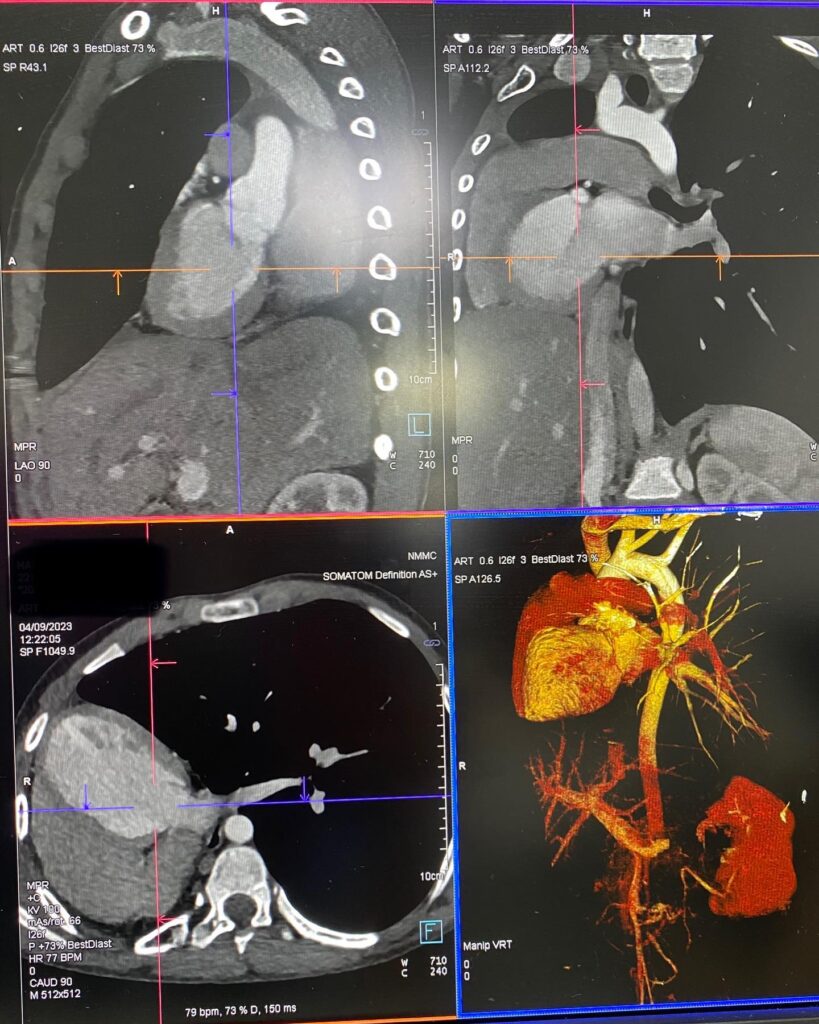

Էխոսրտագրության ժամանակ երեխայի սիրտը աջից էր, սակայն դա սովորական դեկստրակարդիա չէր, ինչը բժշկի մոտ կասկած առաջացրեց, որի կապակցությամբ կատարվեց կրծքավանդակի կոնտրաստ համակարգչային տոմոգրաֆիա։

Արդյունքը տպավորիչ էր։ Երեխայի մոտ առկա էր աջ թոքի ագենեզիա (թոքը չի զարգացել, համապատասխանաբար բացակայում էին նաև աջ գլխավոր բրոնխը, աջ թոքային զարկերակը և աջ թոքային երակները), ինչի հետևանքով միջնորմը (այդ թվում սիրտը) տեղակայված է կրծքավանդակի աջ կեսում։